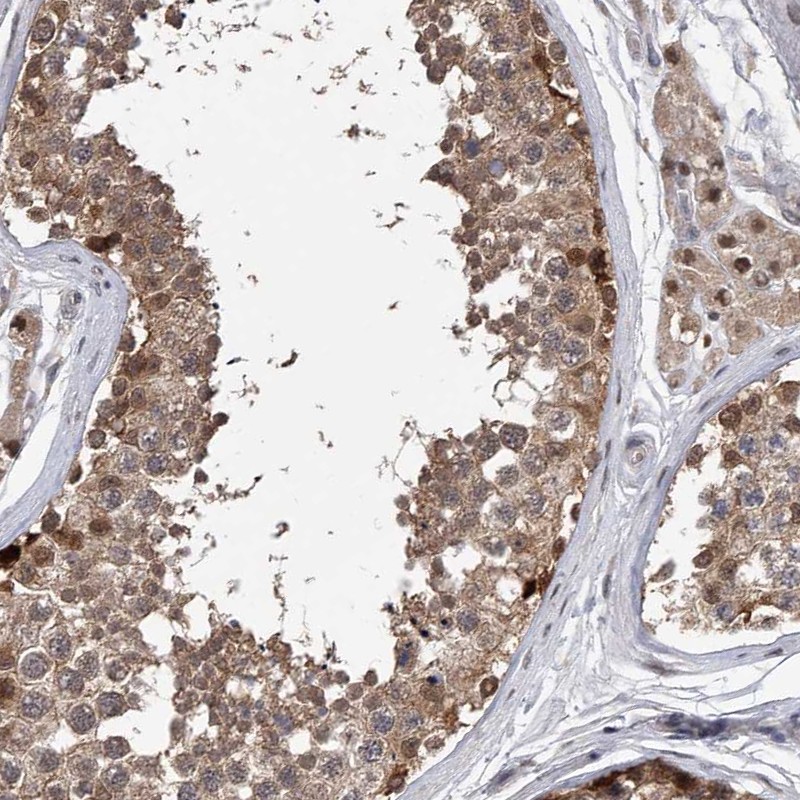

Immunohistochemical staining of human testis shows strong cytoplasmic and nuclear positivity in cells in seminiferous ducts.